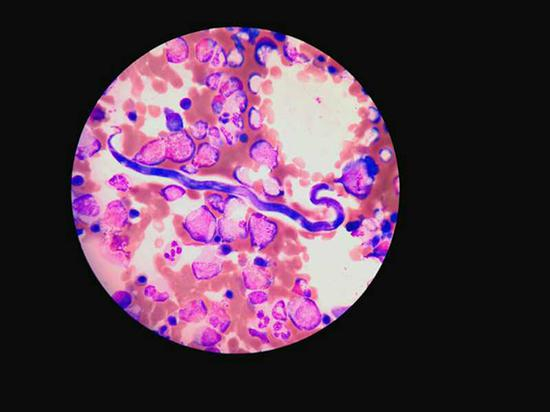

多见于非洲中西部地区的“罗阿丝虫”在显微镜下的形态。 本文图均为 瑞金医院 供图

在检验科主任王剑飙的技术支持下,终于在李艾的骨髓涂片中发现了数量极少的寄生虫微丝蚴。经咨询上海市寄生虫研究所后,断定其为“罗阿微丝蚴”,至此,李艾才被确诊为“罗阿丝虫病”,这在国内是非常罕见的。